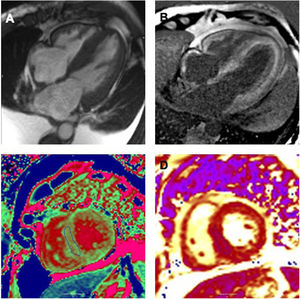

Amiloidosis cardiaca. A) Secuencia cine en 4 cámaras donde se objetiva hipertrofia biventricular, dilatación biauricular y engrosamiento de septo interauricular junto con derrame pleural bilateral. B) Secuencia de realce tardío. Se objetiva realce subendocárdico de forma global en ambos ventrículos y biauricular. C) Secuencia de mapeo T1 nativo. Valor en septo interventricular medio de 1.219ms (valores normales 932-1.053ms). D) Secuencia de mapeo T2. Valor en septo interventricular medio de 47ms (valores normales 44-57ms).